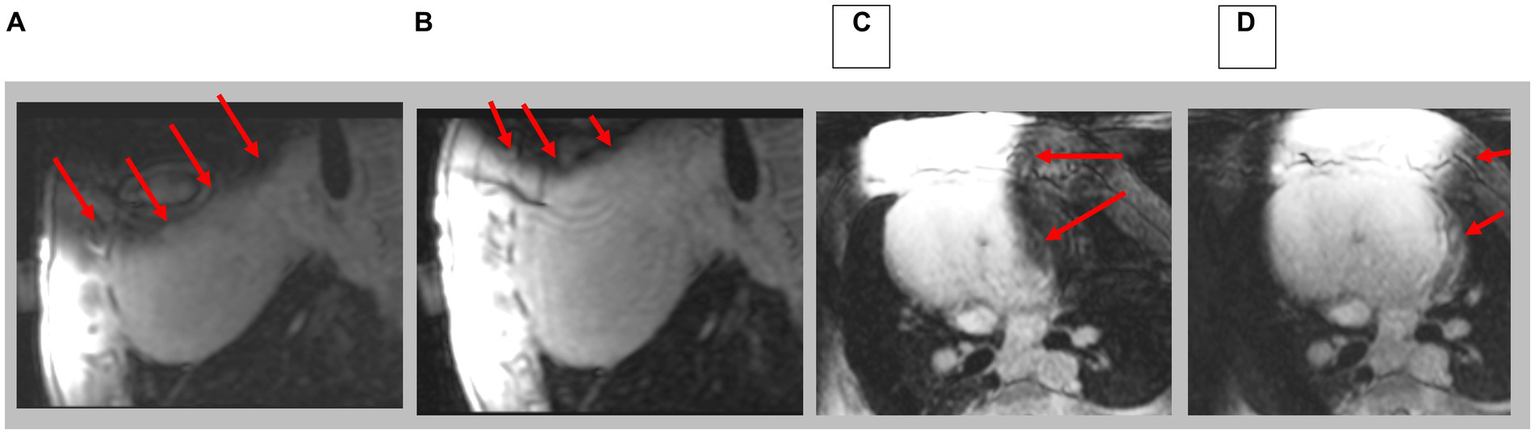

Figure 10

Navigated 3D LGE in sagittal and axial direction; prior to (A,C) and after (B,D) shim correction. Red arrows indicate location of artifacts. Note complete axial image in D.